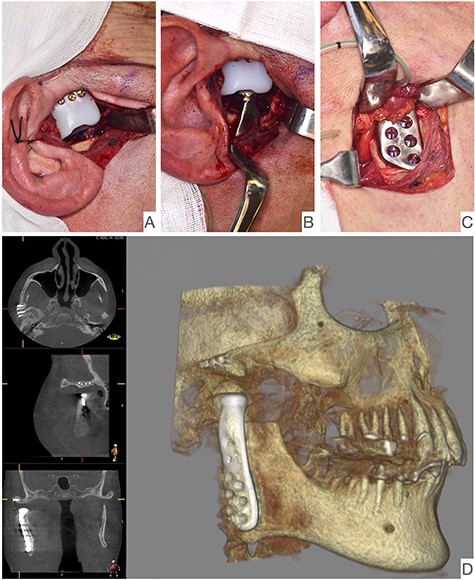

This report is about a 63-year-old patient suffering of bilateral deforming TMJ arthrosis (Wilkes-V) from a bilateral condylar fracture. In 2019 he presented himself to the Department of Oral and Maxillofacial Surgery, showing painful palpation above both TMJs and a severely decreased mouth opening (maximum interincisal distance of 1.5 cm). A computed tomography (CT) scan then revealed pathognomonic changes with flattening of the condyle and articular eminentia as well as partial ankylosis of the right TMJ (Fig. 1). Based on these findings, we decided for a bilateral TMJ-TJR. At this point, the patient only wanted one side replaced for the time being. After impressions were taken, plaster models were 3D-surface scanned and in combination with the CT dataset further processed by Zimmer-BiometTM (Warsaw, USA) for patient-specific TJR (PSI-TJR) fabrication. Another 3 months later, the TMJ-TJR of the right side could be carried out (Fig. 2). Postoperatively the patient received antibiotics for overall 7 days. Satisfied with the result, the patient requested reconstruction of the left TMJ 6 months later. With an improved mouth opening (2.8 cm), impressions were taken using an intraoral scanner. After PSI fabrication, the operation was carried out 9 months after (Fig. 3). Six weeks following surgery, the patient presented with a painful preauricular swelling on the left side, which was diagnosed as aseptic inflammation in the absence of erythema and pathologic joint puncture. Showing a periarticular edema, a broken screw and radial osteolysis around the drilling channels, a subsequent CT scan indicated the loosening of the ultra-high-molecular-weight-polyethylene (UHMWPE) fossa component (Fig. 4). In view of the long production time of new custom-made components and the damaged implant site, we decided to explant the fossa and to temporarily replace it with a non-fixed patient-specific spacer made of COPAL®-bone-cement (Fig. 5) (gentamicin and clindamycin additive) (Haereus; Hanau, Germany). The workflow included the surface scan of the original fossa-drilling template, the computer-aided design of a two-part press mould and the intraoperative fossa fabrication from COPAL®-bone-cement. With the use of a rubber elastic intermaxillary fixation, the vertical mandibular relation could be secured, painful movements and muscle shortening avoided and the risk of perioperative infection could be sufficiently minimized (Fig. 6). After 3 months without complications, the patient-specific COPAL® component could be removed and the new patient-specific UHMWPE fossa inserted within sufficiently regenerated bone (Fig. 7).

Shows postoperative CBCT after left TMJ replacement, 9 months after the right side.